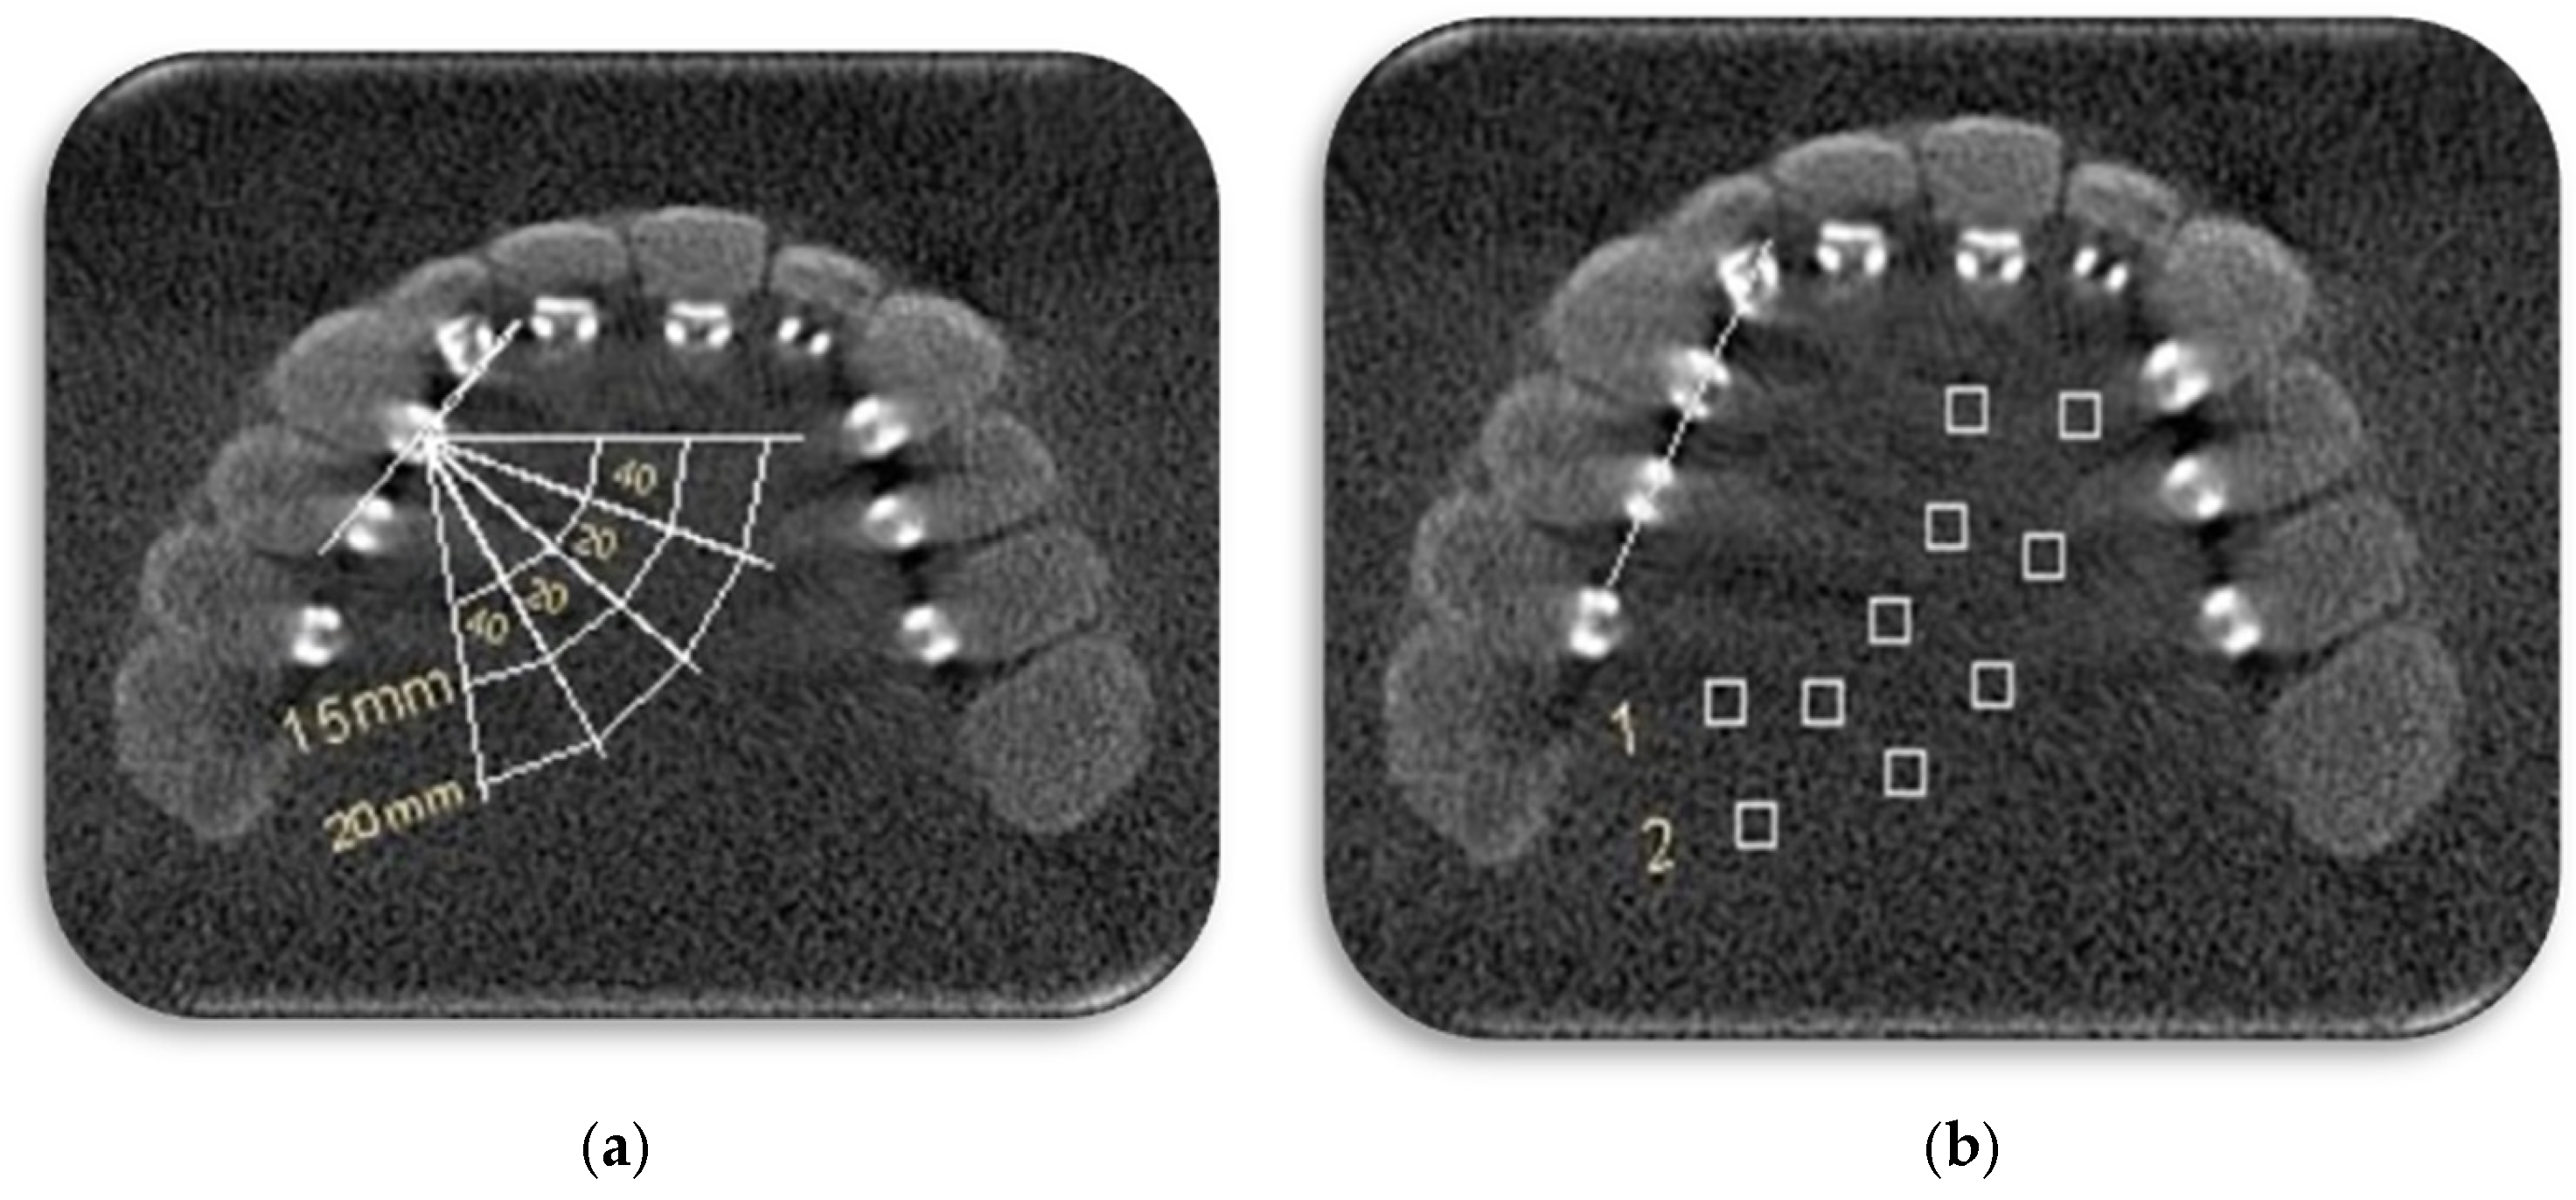

2. Materials and Methods

2.3. Quantitative Analysis of CBCT Images